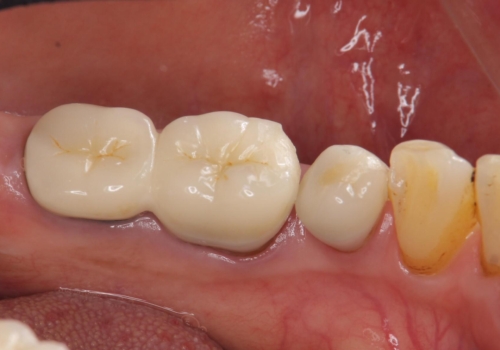

- 他院で右下小臼歯が保存不可能と言われ来院。当院の判断でも残念ながら抜歯となり、欠損部は抜歯後ブリッジにしました。右下奥2本が連結されていたため、そこは各々切り離した形で被せ物のやり替えも行っています。

- 約60万円 右下④5⑥:ジルコニアクラウンブリッジ 11万円×3 仮歯 1万円×3 根管治療費用別途費用は治療当時の料金となります

抜歯後3か月ほど仮歯で生活していただき、欠損部の歯肉の状態が安定してからブリッジを入れています。